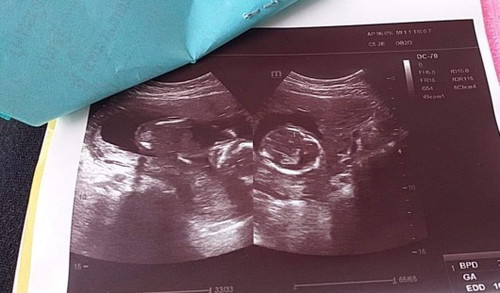

ดูไม่ออกค่ะว่าน้องอยู่สว่นไหนค่ะ

พื้นที่สีดำเป็นน้ำคร่ำ น้องจะเป็นกลมๆค่ะ(รอบหัว)